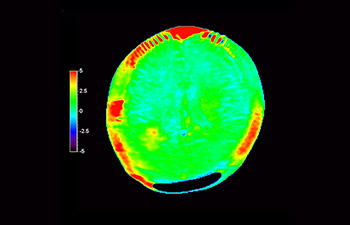

Dans une société où les troubles neurologiques sont importants, Philips s’engage à fournir une qualité de diagnostic irréprochable et la meilleure orientation thérapeutique pour tous les patients. De nos jours, même si l’IRM est une référence en imagerie neuro-oncologique, sa précision en termes de classement des tumeurs et l’évaluation du suivi du traitement peuvent être davantage améliorées. 3D APT (Transfert de proton amide) est une nouvelle méthode d’IRM cérébrale unique et sans contraste qui répond au besoin de fiabilité pour les diagnostics neuro-oncologiques. 3D APT utilise la présence de protéines cellulaires endogènes pour produire un signal RM qui est directement lié à la prolifération cellulaire, indicateur de l’activité tumorale. 3D APT peut aider les professionnels de santé formés à différencier les gliomes cérébraux de haut grade par rapport aux gliomes cérébraux de bas grade, ainsi que l’évolution de la tumeur par rapport aux effets du traitement1.

avec 3D APT